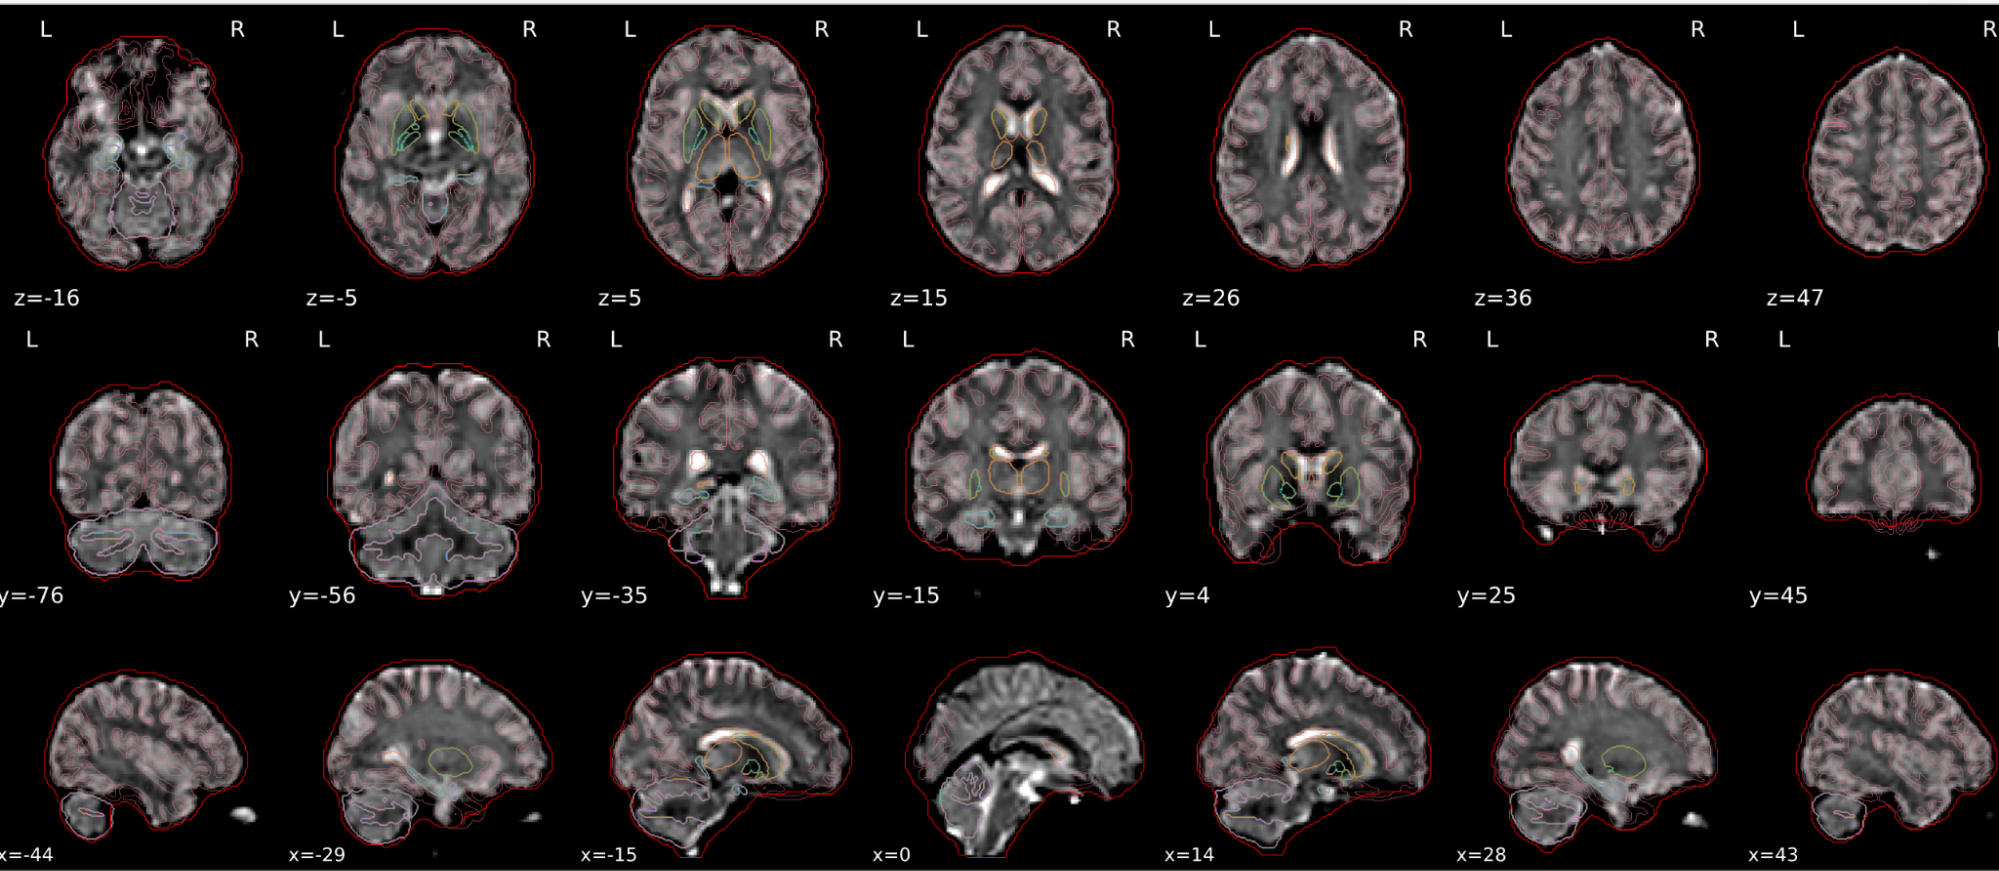

EPI spatial normalisation

This QC step shows the registration of the EPI image to MNI space.

Example of a good subject

- If the registration performed well, you should see an overlap (i.e., correspondence of structures) between the MNI template and the EPI registered to the MNI space.

- If parts of the brain are missing due to the scanner field of view, this is fine. For example, the cerebellum may be cut off for a participant with a large head.

Example of a bad subject

- In case of poor registration, you should see a misalignment of the EPI and the MNI template

Summary

| good | bad |

|---|---|

| Overlap (i.e. match of structures) between the MNI template and the EPI registered in the MNI space | Misalignment of the EPI and the MNI template |

| If parts of the brain are missing because the field of view of the scanner is limited, the EPI spatial normalisation does not have to be excluded e.g. cerebellum cut off in person with large head |

If parts of the brain are missing because the field of view of the scanner is limited, the EPI spatial normalisation does not have to be excluded (e.g. cerebellum cut off in person with large head)